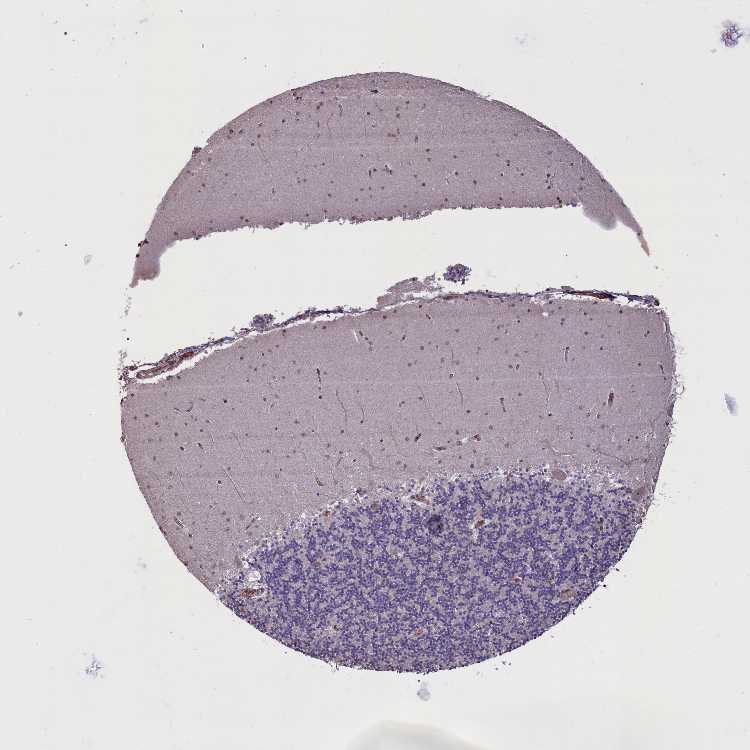

CEREBELLUM - Antibody stainingi

Antibody staining in the annotated cell types in the current human tissue is reported as not detected, low, medium, or high, based on conventional immunohistochemistry profiling in selected tissues. This score is based on the combination of the staining intensity and fraction of stained cells.

Each image is clickable and will lead to virtual microscopy that enables deeper exploration of all samples and also displays staining intensity scores, fraction scores and subcellular localization as well as patient and tissue information for each sample.

Antibody HPA042001

Purkinje cells Medium

Cells in granular layer Not detected

Cells in molecular layer Medium